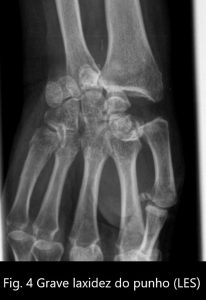

O LES manifesta-se de forma algo diferente. As erosões ósseas características da AR ocorrem de forma muito menos exuberante, ou estão ausentes. Por outro lado, afetam de forma muito mais intensa as estruturas capsulo-ligamentares, provocando-lhe grande laxidez e consequentemente sub-luxações e luxações. (ver figuras 4 e 5)